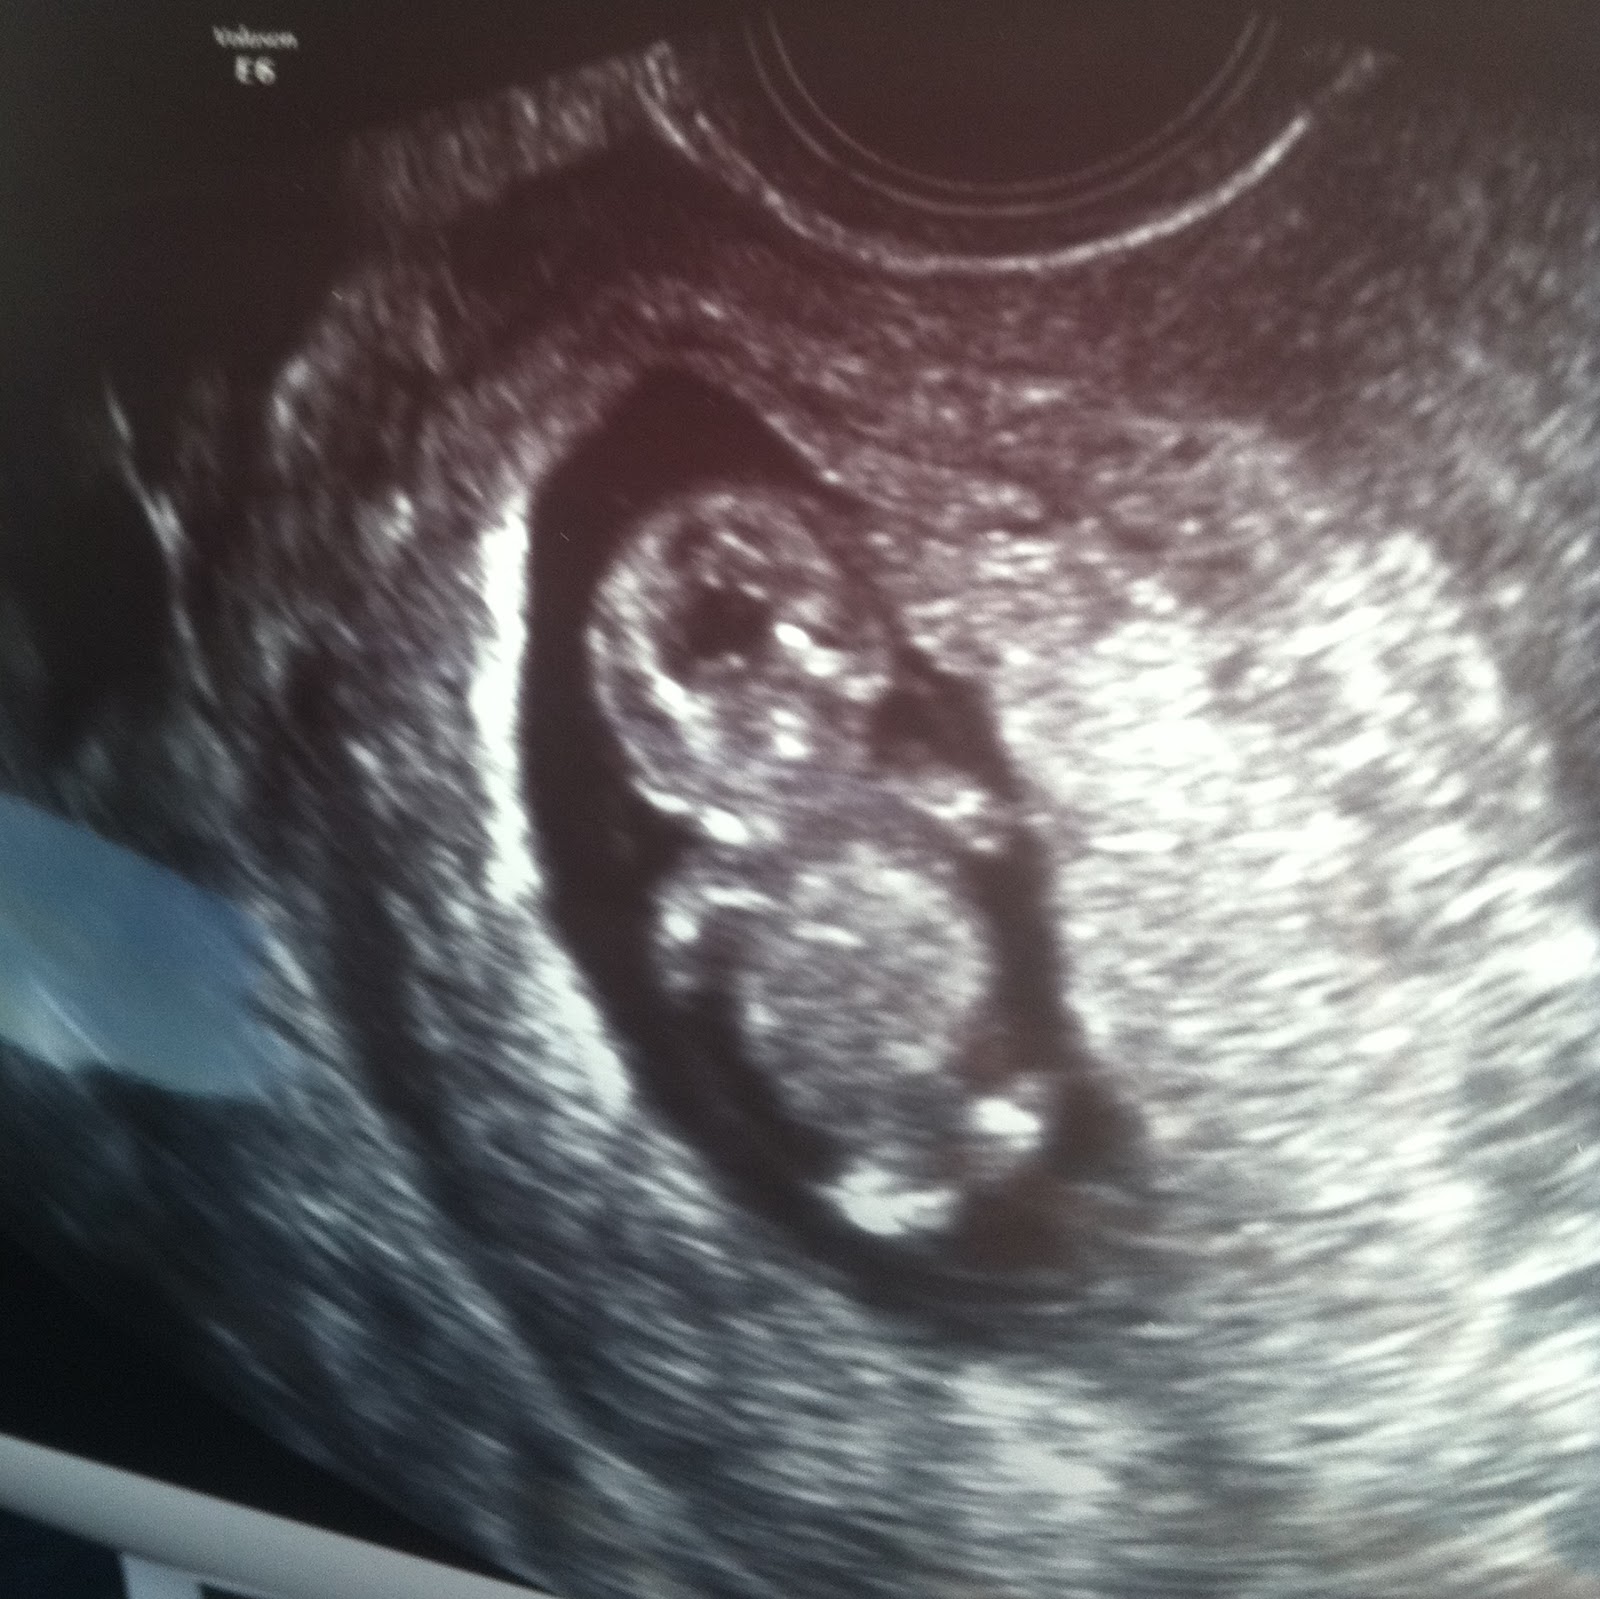

10 Week Ultrasound Everything You Need to Know MyBump2Baby